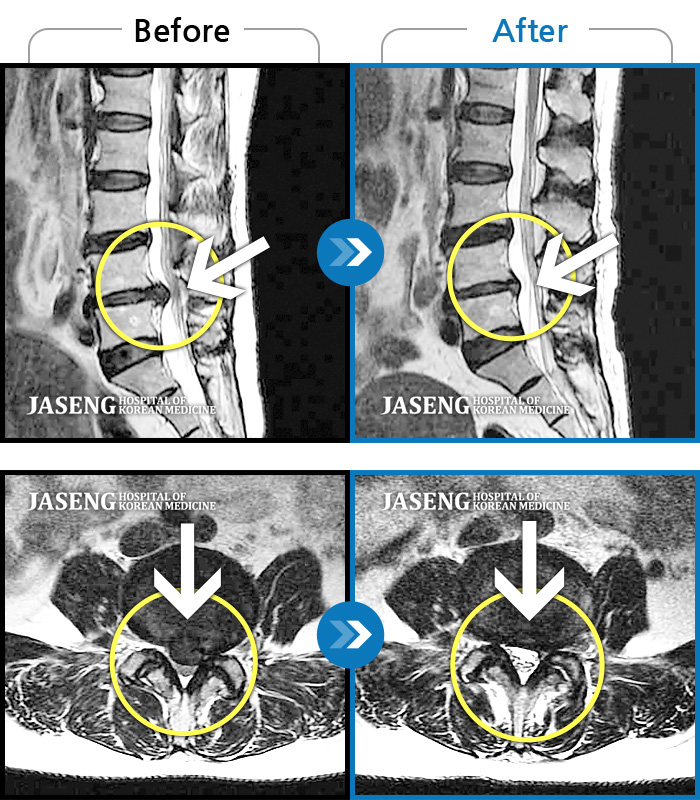

MRI사진에서 좋아지고 있다는 말씀에 넘 기뻤습니다^_^